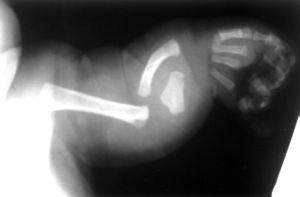

Los hallazgos radiológicos confirmaron el diagnóstico de DML: acortamiento de los huesos largos de extremidades, más marcado en antebrazos y piernas con marcada angulación de la diáfisis radial, cúbito ancho y corto, deformidad de la cabeza humeral (fig. 1); cuello femoral corto con grandes trocánteres y cóndilos, acortamiento, ensanchamiento y angulación lateral de la tibia con hipoplasia de peroné a expensas de su porción proximal (fig. 2) e hipoplasia mandibular. El cariotipo fue normal, 46 XY. No se encontraron malformaciones asociadas.

Figura 2. Acortamiento y ensanchamiento tibial con hipoplasia de peroné especialmente en su porción proximal.